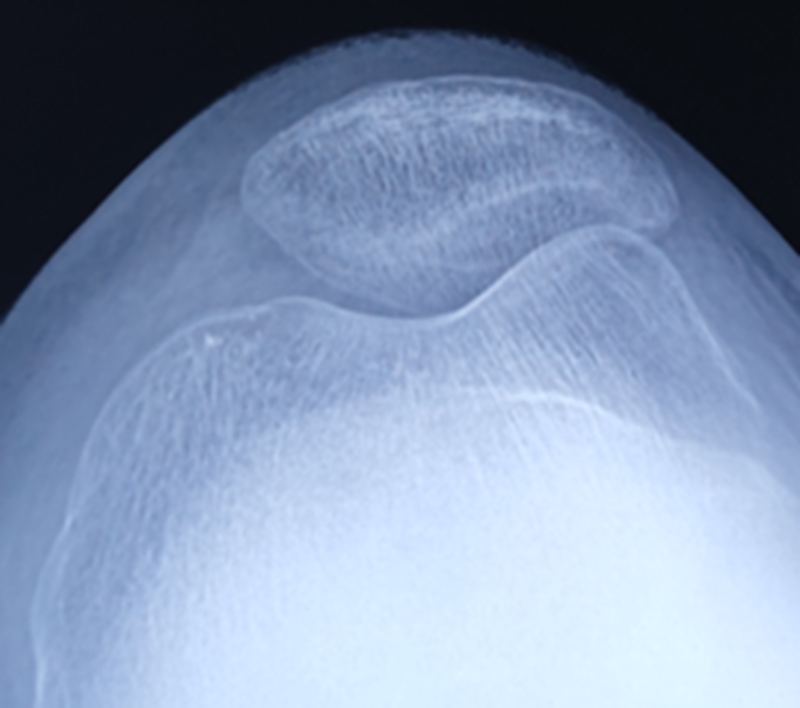

术前X线

术后X线